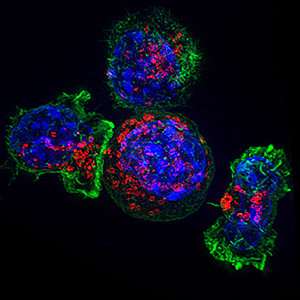

Immagine: cellule T citotossiche (a sinistra) che coinvolgono una cellula tumorale (cellula rotonda, centro). Credito: NIH. L’infiammazione cronica è nota per guidare…